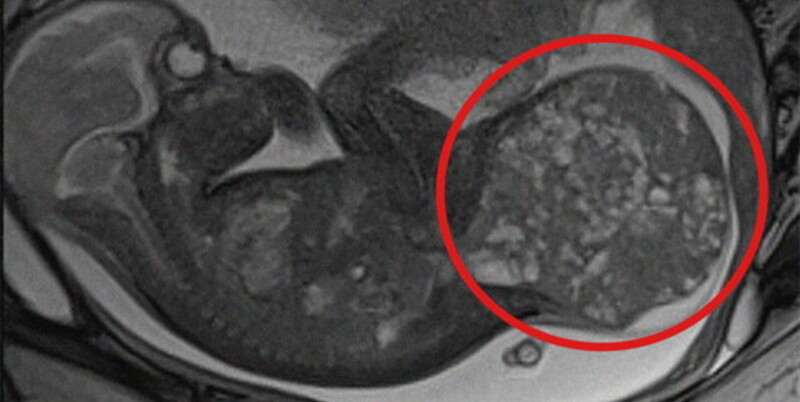

La grande massa rimossa, un teratoma sacro-coccigeo, è una rara neoplasia che si sviluppa nella parte terminale della colonna vertebrale e colpisce circa 1 neonato ogni 35.000-40.000 nati vivi. Pur essendo solitamente benigna, può comportare gravi complicanze per il feto. Tra queste il rischio di scompenso cardiaco, idrope fetale e morte intrauterina.

Nel caso specifico, alla 28esima settimana di gestazione, a seguito di una rapida e improvvisa crescita della massa tumorale, gli specialisti dei due ospedali hanno deciso di intervenire in epoca fetale con una procedura mininvasiva di lasercoagulazione ecoguidata dei vasi sanguigni della massa stessa, eseguita presso il comparto operatorio del San Pietro Fatebenefratelli. Utilizzando un laser a diodi è stato possibile ridurre l’afflusso sanguigno al tumore, rallentandone la crescita e permettendo di prolungare la gravidanza fino alla 30esima settimana.

La gestione multidisciplinare è proseguita all’Ospedale Pediatrico Bambino Gesù, dove la mamma ha poi partorito con parto cesareo programmato nell’ambito del ‘Progetto Nascita’ dedicato ai nascituri affetti da gravi patologie congenite. Dopo essere venuta alla luce, la neonata (che prima dell’intervento pesava 1,9 chili) è stata immediatamente operata per rimuovere completamente il teratoma di circa 800 grammi, pari ad oltre la metà del suo peso corporeo effettivo (1,1 chili). L’operazione, della durata di circa 3 ore, ha incluso anche la ricostruzione della regione sacrale.